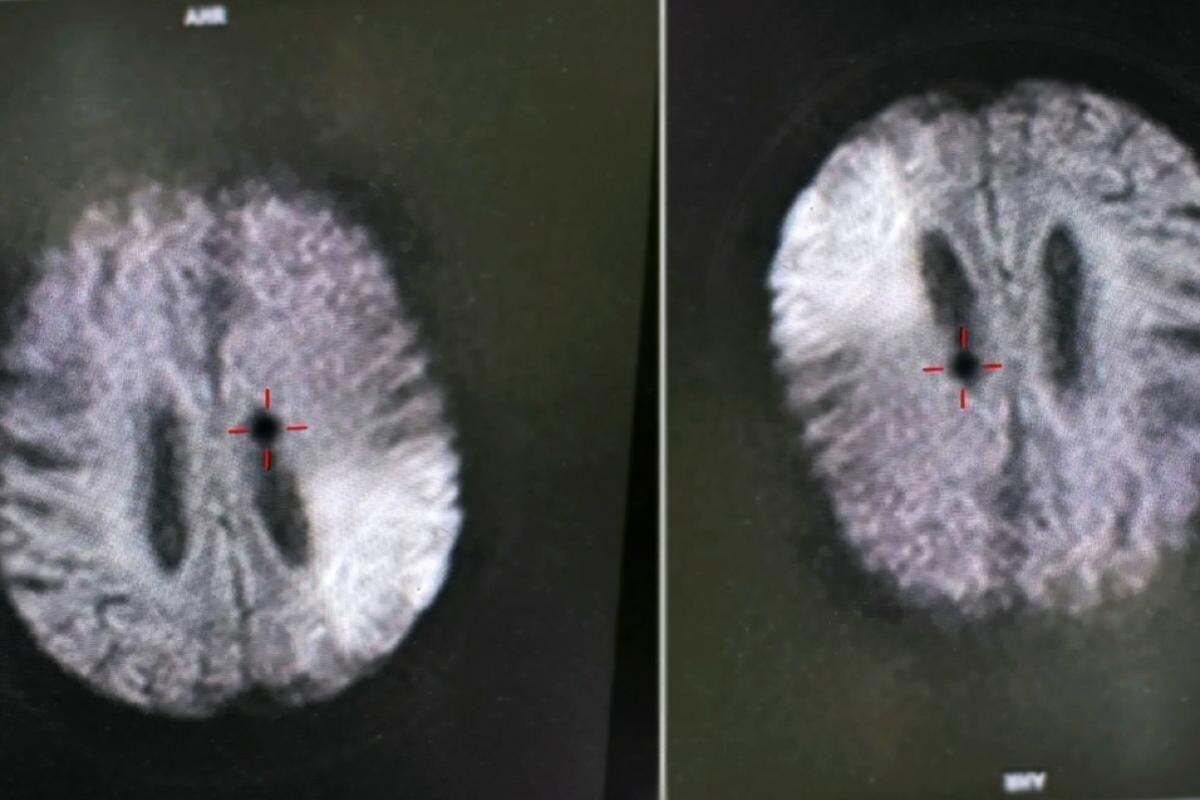

45-летний житель Рязани был экстренно доставлен в Областную клиническую больницу в тяжёлом состоянии после инсульта. Как сообщили в региональном министерстве здравоохранения, мужчину без сознания обнаружила дома его супруга. Пациент не мог вспомнить момент потери сознания, а до происшествия, по его словам, чувствовал себя нормально. Скорая помощь прибыла оперативно и доставила его в приёмное отделение ОКБ, где медики диагностировали острое нарушение мозгового кровообращения. Специалисты незамедлительно начали проведение тромболитической терапии, направленной на растворение тромба и восстановление кровотока в поражённой зоне мозга. Благодаря слаженным действиям врачей, состояние пациента удалось стабилизировать. В течение 10 дней он находился под пристальным наблюдением в стационаре. На 11-й день мужчина был выписан, состояние здоровья — удовлетворительное.